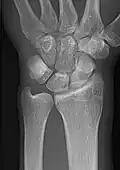

Extremities

A projectional radiograph of an extremity confers an effective dose of approximately 0.001 mSv, comparable to a background radiation equivalent time of 3 hours.[16]

• Radius and Ulna - AP and Lateral

• Wrist - DP and Lateral

• Scaphoid - DP with Ulna deviation, Lateral, Oblique and DP with 30° angulation

Certain suspected conditions require specific projections. For example, skeletal signs of rickets are seen predominantly at sites of rapid growth, including the proximal humerus, distal radius, distal femur and both the proximal and the distal tibia. Therefore, a skeletal survey for rickets can be accomplished with anteroposterior radiographs of the knees, wrists, and ankles.[20]